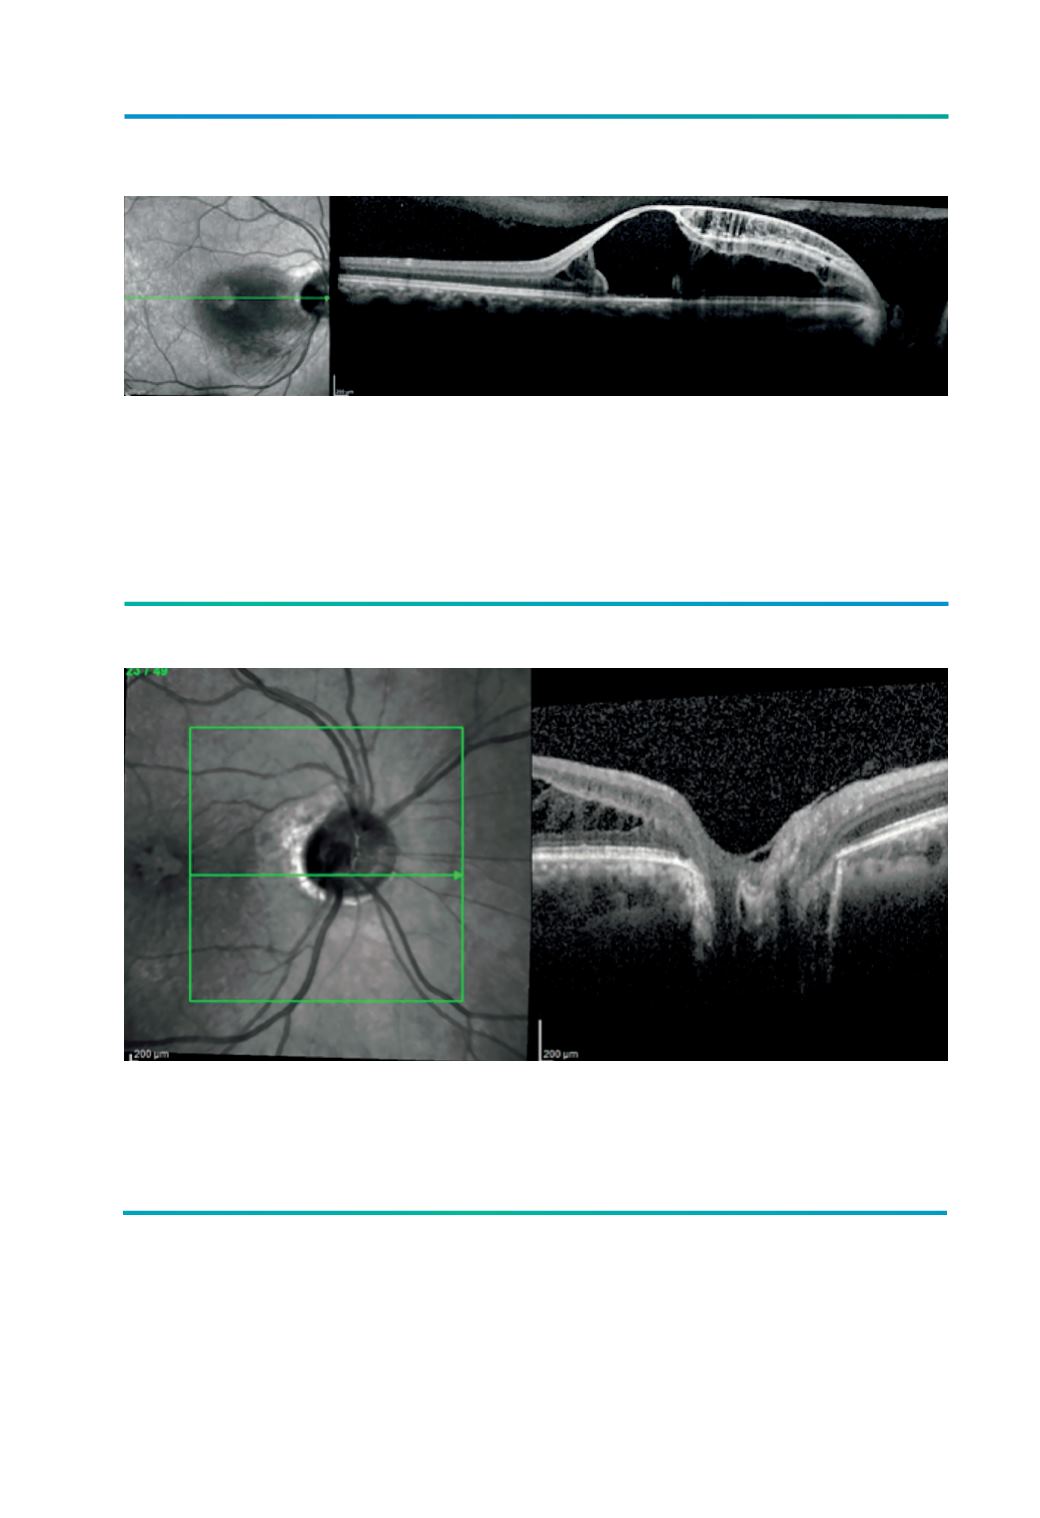

Figura 4.

OCT com corte na parte central da fosseta do doente da figura 3 onde se evidencia a presença de fluido em

múltiplas camadas da retina (“retinosquisis multicamada”): na camada das células ganglionares, na camada

nuclear interna, na camada plexiforme externa e na camada nuclear externa. A presença de um pequeno

descolamento da retina foveolar está subjacente a um buraco lamelar externo (defeito na camada externa

retiniana). De realçar a presença de um descolamento posterior do vitreo parcial sem identificação de adesão

vítreo-retiniana neste corte.

Figura 5.

OCT do doente da figura 3 com corte ao nível do bordo inferior da fosseta onde se consegue identificar a presença

de uma membrana com contiguidade entre o bordo da papila e o bordo da fosseta associada a algum grau de

aderência vítrea.